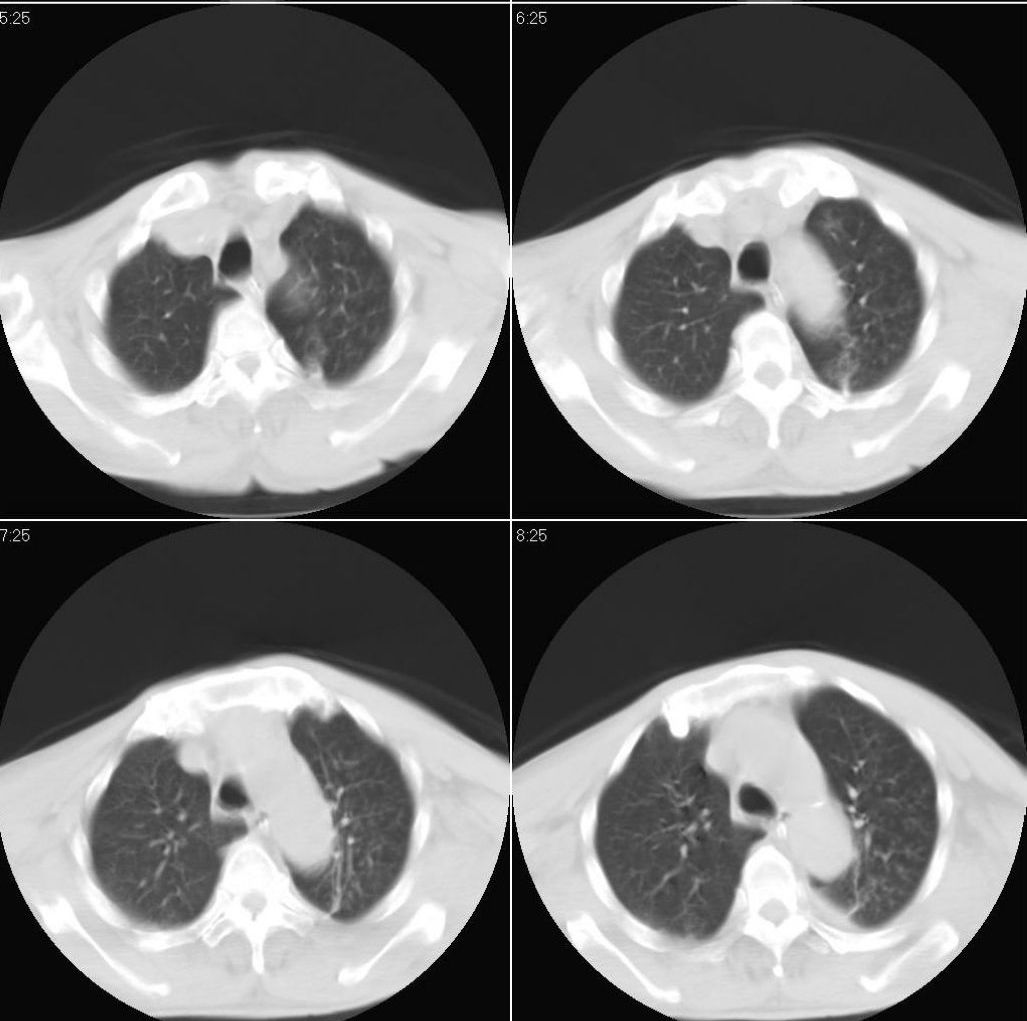

男性,65岁。因外伤来诊。该患者因脑外伤住院。以下是今天的dr和ct:

一周前胸片无异常,不考虑肿瘤,现x片及ct表现应与外伤有关,考虑左侧外伤性膈疝,并左下肺不张。右肺挫裂伤。少量胸水。

一周前胸片无异常,不考虑肿瘤,现x片及ct表现应与外伤有关,考虑左侧外伤性膈疝,并左下肺不张。右肺挫裂伤。少量胸水。支持

1 外伤性左侧膈疝、胸腔积液致左肺下叶不张 2右肺挫伤

右侧第7肋骨腋段骨折并右肺挫伤;左侧膈疝并肺不张。

左侧膈疝并左下肺膨胀不全,,【左下支气管腔变狭窄随诊除外堵塞病变】右肺散在炎症。